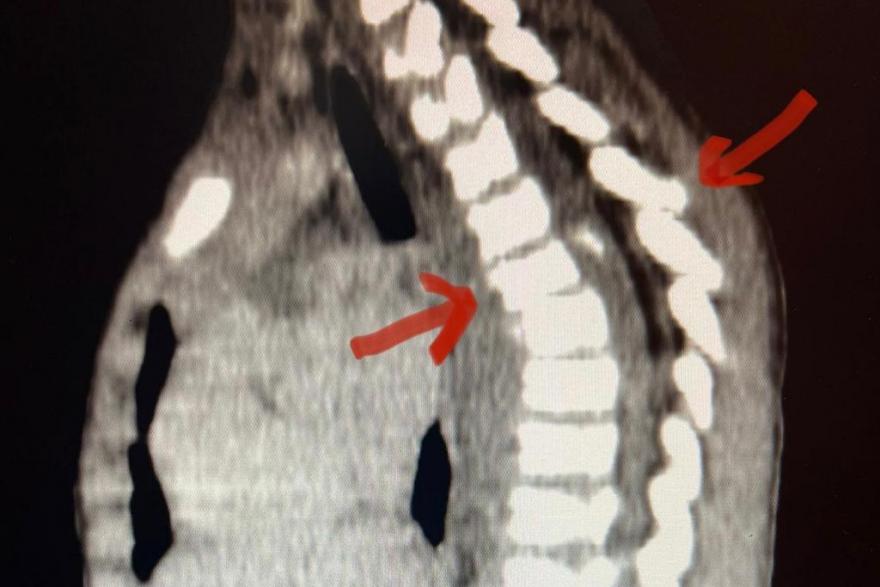

Нейрохирурги из медицинского центра Илизарова прооперировали 3-летнего мальчика, который выпал из окна 3 этажа.

Позже пациента перевели в Клинику патологии позвоночника и редких заболеваний. Там его прооперировали - стабилизировали позвоночник металлоконструкциями. По словам врачей, маленький пациент чувствует себя удовлетворительно.